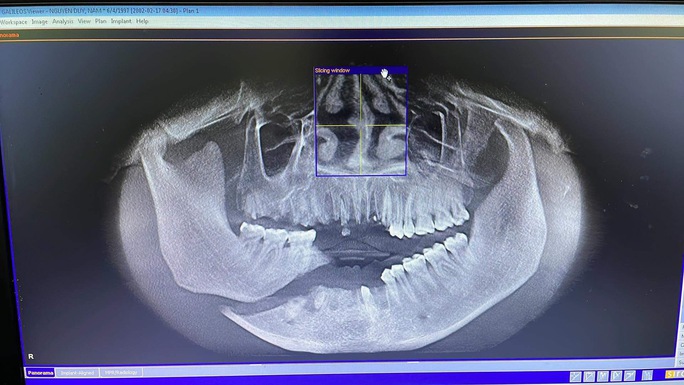

Trước đó, bệnh viện cũng tiếp nhận nam bệnh nhân 26 tuổi (ở Hà Nội) bị vỡ nát xương hàm dưới phải, vỡ xương ổ răng hàm trên, dưới vùng cửa, mất toàn bộ răng cửa trên, dưới do thang máy trong nhà đang sửa chữa cuốn cả người vào trong lúc nhặt điện thoại rơi.

Bệnh nhân đã được phẫu thuật cấp cứu sau đó. Cách đây ít ngày, bệnh nhân đã quay trở lại bệnh viện cắm implant để có thể ăn nhai bình thường.